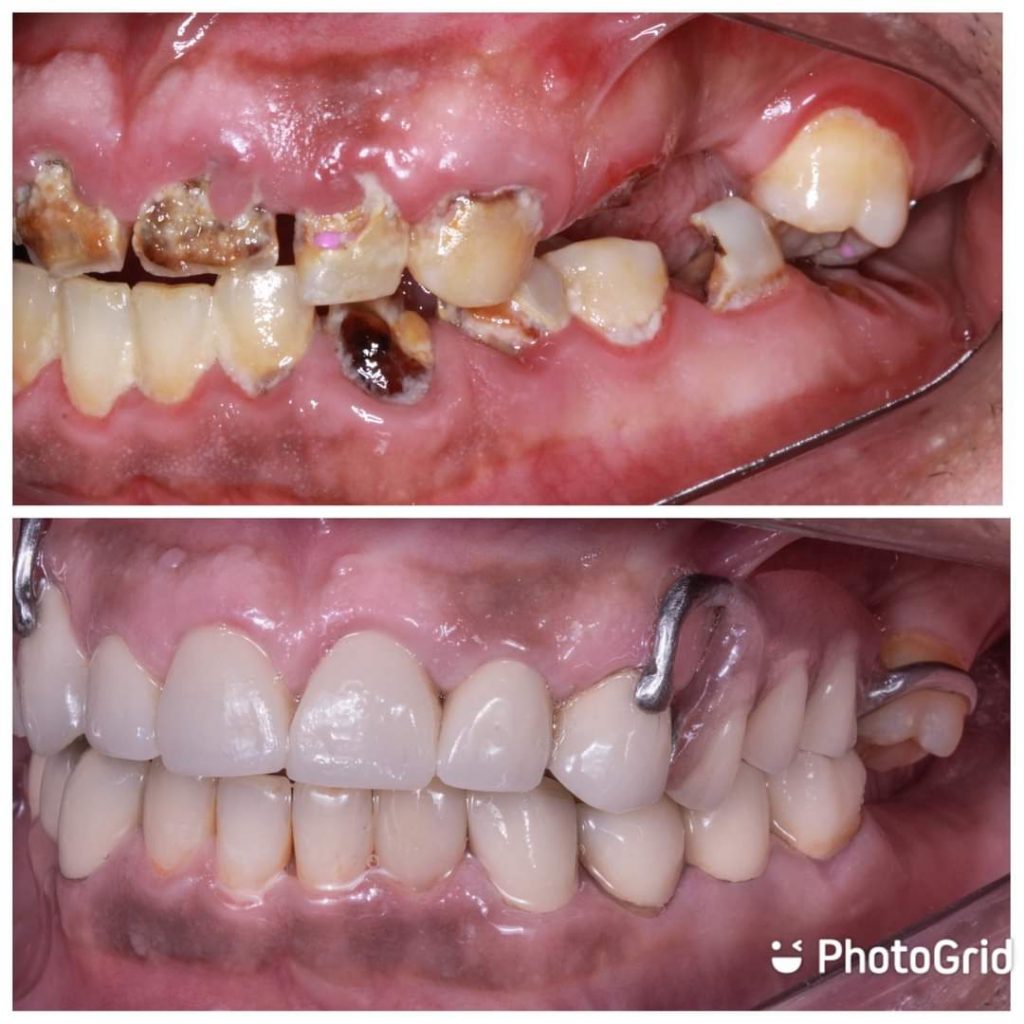

Hi this is my first full mouth rehabilitation case as graduation project .

In this case , I start extra-oral analysis to determine ricketts angle plane for maxillary anterior crowns protrusion to overcome crossbite.

Excavation for all caries lesion to stop carious process .

After, proper diagnosis,radiographic and clinical examination , endodontic treatment was done for teeth no 13,12,11..21,22 also, teeth no 33, 34,36

Then, fiber posts and composite cores were performed to badly destructed teeth

PFM crowns on 13,12,11,21,22,23,33,34,35,36